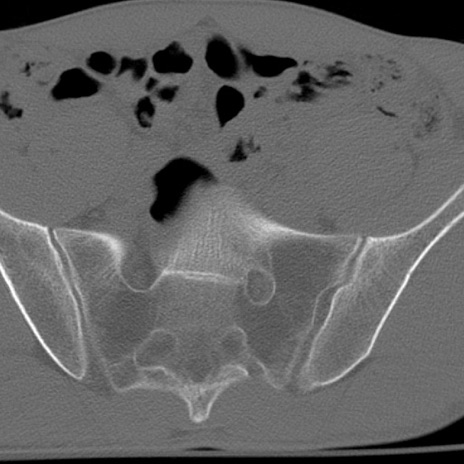

症例3 腰椎CT(横断像)

腰椎CT